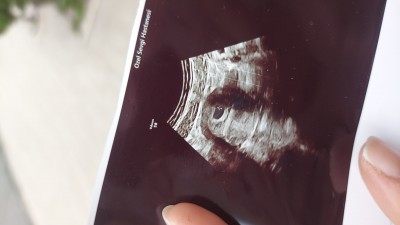

Kızlar 5+3 hamileyim çok şükür.  Bugun doktora gittik ilk kez kese var haftasiyla uyumlu.bebekle ilgili bisey demedi doktorum .15 gün sonra kalp atışı için gel dedi. Nisan ayinda bir kaybım oldu biraz evhamliyim. Kızlar 15 günde hem bebeğim hemde kalp atışı belli olur mu ? ♡

Gebelik haftası 5+3